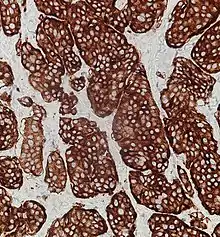

Synaptophysin immunohistochemistry of neuroendocrine tumor, staining positively.

Given the diverse secretory activity of NETs there are many other potential markers, but a limited panel is usually sufficient for clinical purposes.[2] Aside from the hormones of secretory tumors, the most important markers are:

• synaptophysin (P38)